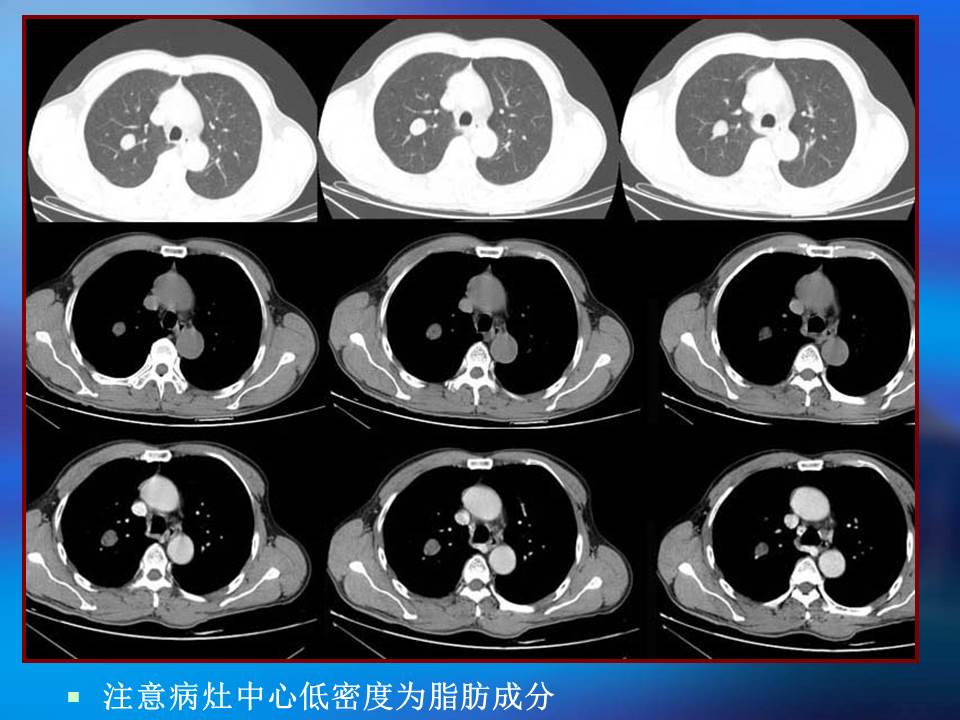

肺良性肿瘤